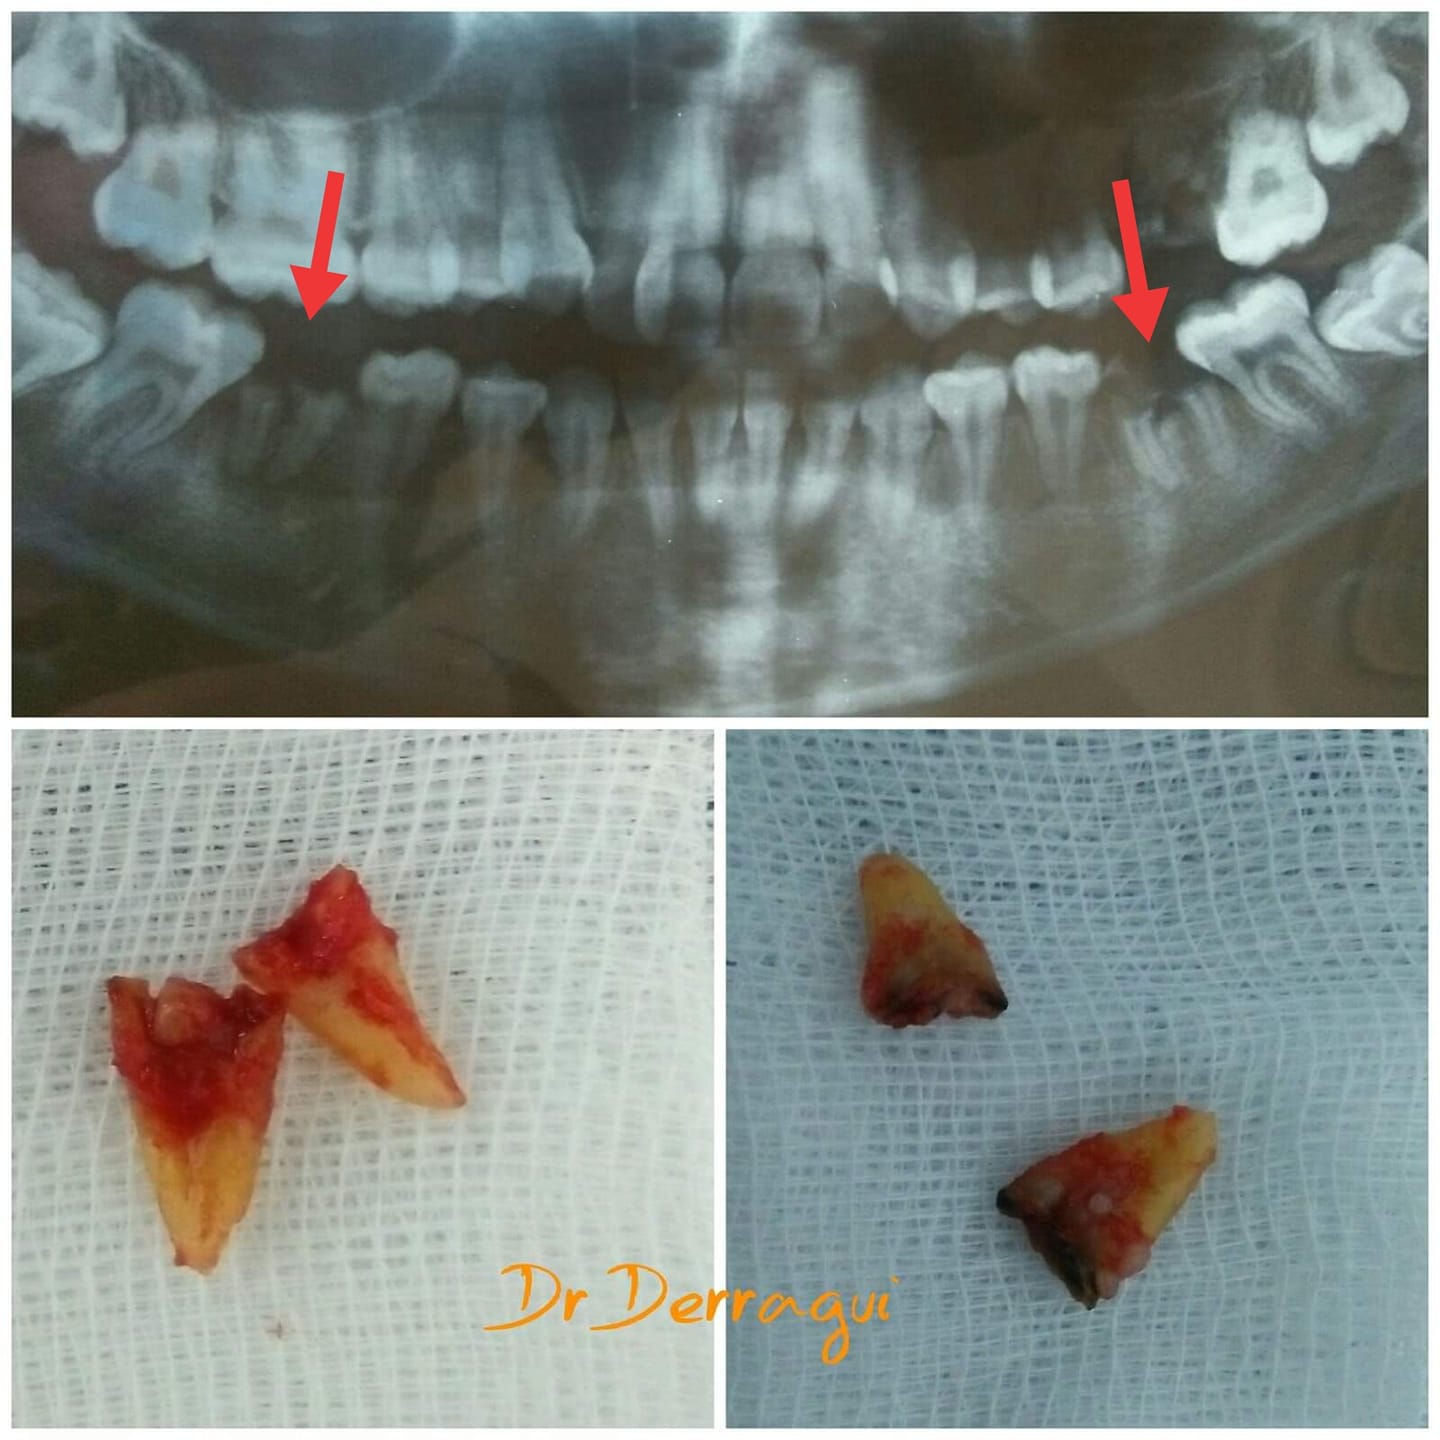

Chirurgie et extractions

Des interventions sûres et douces, réalisées avec une précision chirurgicale.

Nos interventions incluent les extractions complexes et les dents de sagesse.

Chaque geste est planifié et sécurisé pour garantir un rétablissement rapide et sans douleur.

La chirurgie dentaire au service du confort et de la confiance.